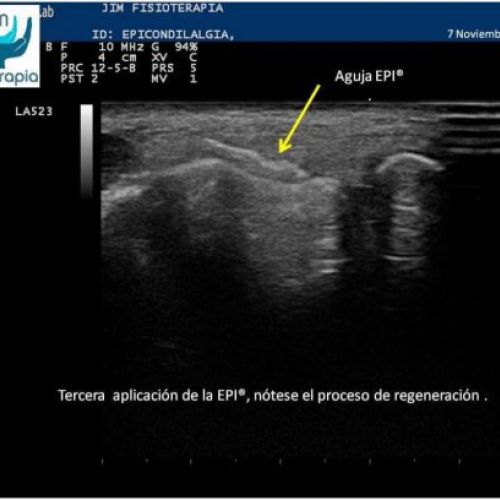

Tratamiento de epicondilitis con EPI®

EPI® Fisioterapia en Madrid para el tratamiento de la epicondilitis